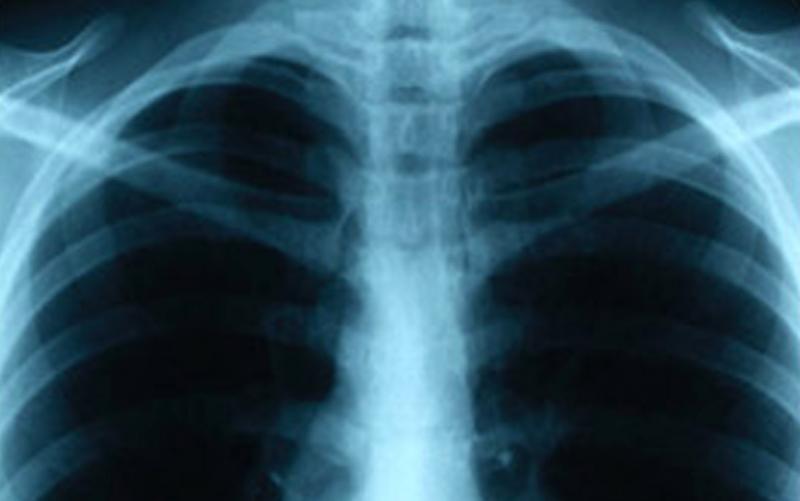

An individual at Lincoln High School was recently diagnosed with tuberculosis (TB) and may have exposed students and staff, the County Health and Human Services Agency (HHSA) reported today.